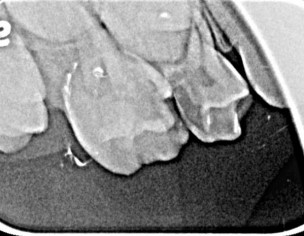

My daughter is 7 and hav deep cavity I took her to dentist one said she need 1 extraction and when I went to pediatric dentist she said she needs 4 extractions which she is going to do altogether same day I am attaching her xrays can any dentist plz advise after looking at the xrays thanks

Her both upper D are definitely for extraction and for her E need to evaluate clinically as well there might get b some Endodontic treatment and space maintainers afterwards

After extraction she will need space maintainer to keep first molar in its place so better to go for RCT to keep this tooth till age 12